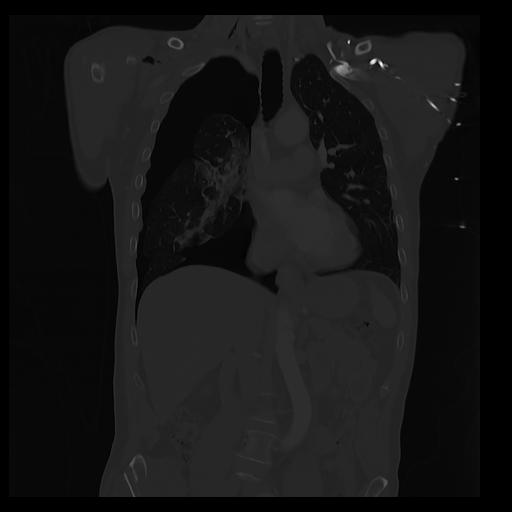

32 PULMON,CE,Coronal,3.000,PULMON,Coronal,